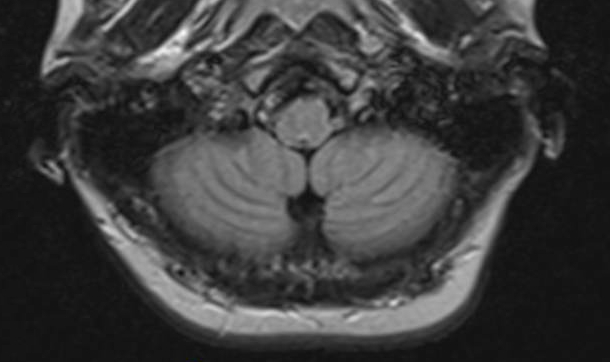

Over time, "significant and persistent" MRI abnormalities (called T1-weighted signal hyperintensities) developed in the brains of rats receiving the linear GBCA, gadodiamide. But no MRI abnormalities appeared in the brains of rats injected with the macrocyclic agent, gadoterate meglumine.

The increases in signal hyperintensity persisted even after the injections stopped. In subsequent examinations, high total gadolinium concentrations were measured in the deep brain (cerebellum) of gadodiamide-treated rats, corresponding to the area of the MRI abnormalities.

The findings are consistent with recent studies reporting T1 hyperintensities in human patients receiving multiple injections of linear GBCAs for MRI scans. "Certain of these agents lead to heavy-metal deposition in parts of the brain, which is not seen with the macrocyclic GBCAs," said Runge.